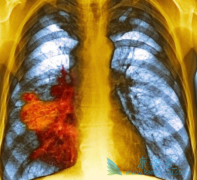

肺癌PD-1抗体药物Opdivo在中国的价格是美国的一半

在中国这个吸烟大国, 肺癌 可是被称为“癌症第一杀手”。在过去的三十年间,我国肺癌患者死亡率上升了465%,肺癌也因此成为上升速度最快的癌症,并且已取代肝癌成为我国癌症导致死亡的首要原因。   肺癌主要分为非小细胞肺癌和小细胞肺癌两种,其中非 ...